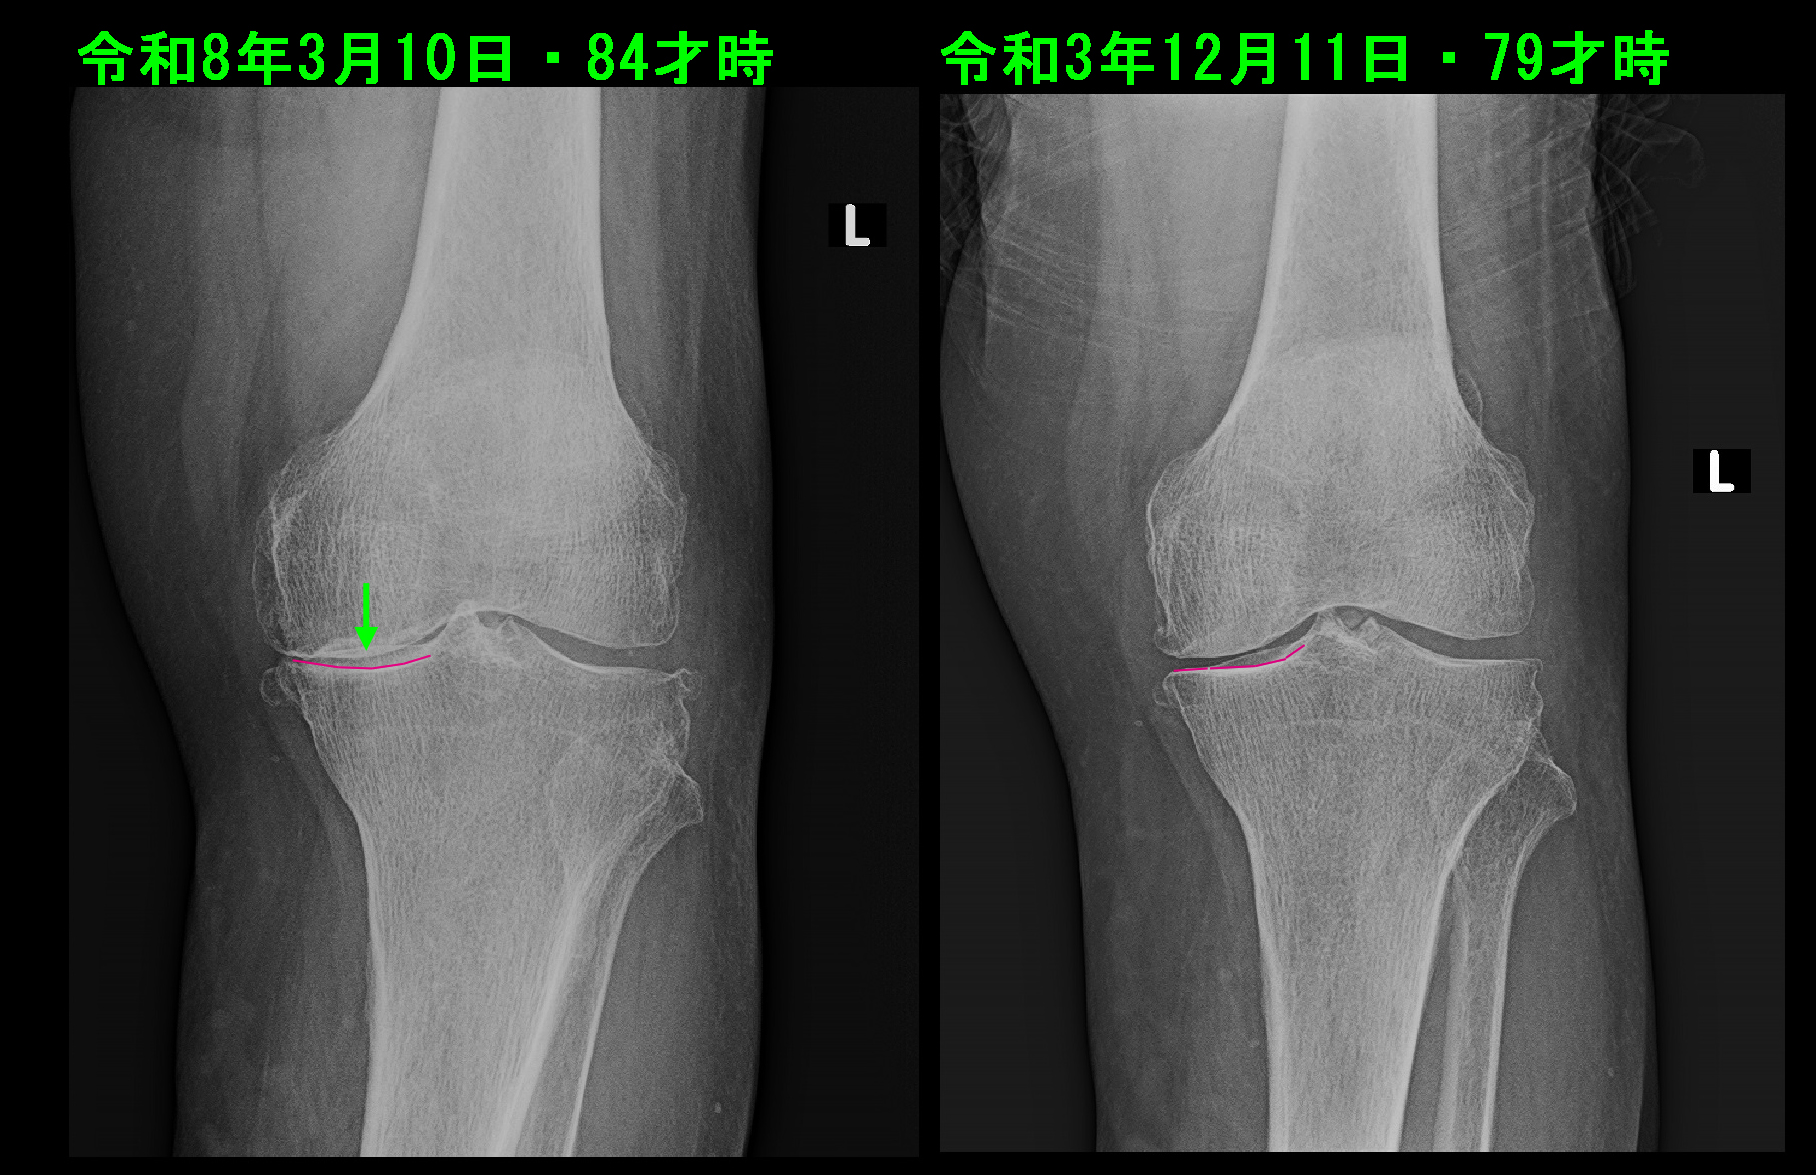

変形性膝関節症における変形と老化の進行について、比較的良好なタイプと良好でないタイプの老化の進行があります。それを提示してみたいと思います。

84才男 Xp.jpg

まずは、良好なタイプの老化の変形の進行を提示します。84才の男性ですが、令和3年12月11日の79才時の左膝レントゲン像に比較すると、令和8年3月10日のレントゲン像では内側の関節裂隙は軽度狭くなっています。下腿側の脛骨の内側の関節面はその中央部が凹むような形状となっています。このような変形では大腿骨からの体重は下方に伝達され、膝の体重伝達様式としては安定した状態です。膝痛があっても歩行も不安定となることはありません。

84才女 Xp.jpg

それに対して、令和3年11月29日80才で左膝痛で受診された女性です。初診時より左膝の内側の関節裂隙は消失しており、重度の変形性膝関節症です。保存的治療としてヒアルロン酸製剤関節内注入療法を断続的に継続していました。3年8か月後の令和7年7月の左膝関節のレントゲン像は、内側の関節軟骨が消失した状態は変わりありませんが、下腿側の脛骨の内側の骨の関節面が平坦な状態から摩耗して傾斜するようなラインとなっています。時々脛骨の内側部分がこのような傾斜するように摩耗する変形が進行していく方がいますが、このような変形では大腿部は体重がかかることで内側にずれる力が働きます(緑矢印)。このような変形ではこのホームページの「当院のリハビリテーション」のページの“86才女性 重度変形性膝関節症の不安定歩行のリハビリ”のような歩行状態となっていきます。膝痛が悪化するだけでなく、歩行が不安定となり、転倒のリスクも高まることになります。手術を受けなければ車イスの生活にならざるをえなくなってしまいます。注意を要する老化の変形です。その予防について明確な方針はありませんが、当院ではリハビリテーションを適応して、歩行の安定を図る試みを行っています。